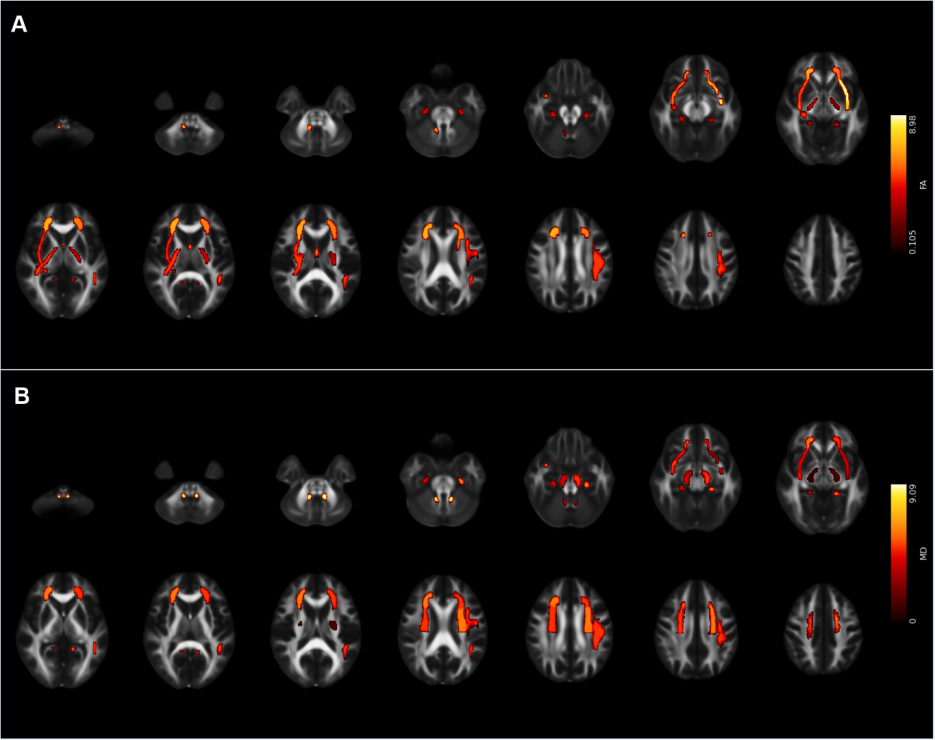

研究团队招募了49名4-12岁的孤独症儿童,实验组进行了为期12周以小篮球形式为主的团体互动型运动技能学习,对照组则接受常规护理。本研究除了采用自行研发的适用于孤独症儿童共同注意任务外,还采用了眼动追踪技术和磁共振扫描手段,对所有被试进行了基线水平和12周后的数据采集。结果发现,实验组儿童在经过运动干预后,共同注意显著提高,线索首次注视时间也到了显著改善;同时,上纵束、额枕束、扣带、钩状束等联络纤维以及放射冠、内囊、外囊、大脑脚等投射纤维完整性显著增强。

图1. 干预后,在FA (A)和MD (B)存在显著交互作用的白质区域

此外,研究结果发现,实验组儿童所发现的减少的首次注视时间与降低的左侧上放射冠和左侧上额枕束平均弥散率呈显著正相关。这表明,篮球运动技能干预有效改善了孤独症儿童的共同注意力,其改善机制可能与感觉感知、空间和早期注意功能相关的白质纤维完整性变化有关。